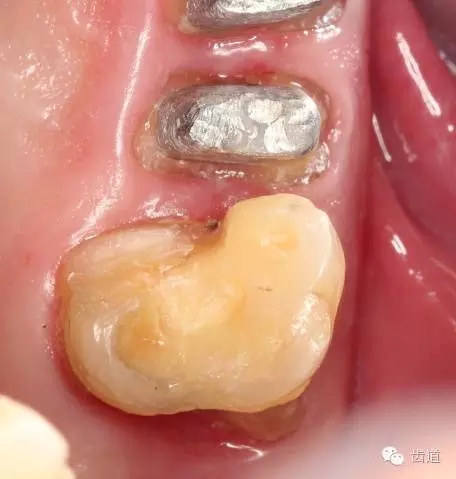

1、磨牙近中崩折舌面行嵌體牙體預(yù)備后

2、金屬鑄造嵌體

3、磨牙金屬鑄造嵌體粘固后